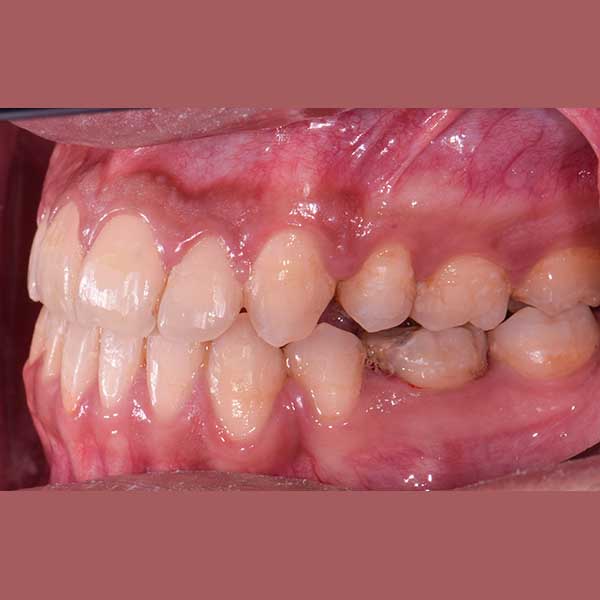

“راجعتني هذه الشابة قبل عدة سنوات وهي تعاني من ازدحام شديد في أسنانها، لدرجة أن أحد أنيابها قد بزغ بشكل مرتفع وبعيد عن مكانه الطبيعي. طلبت مني صديقتنا مساعدتها وترتيب أسنانها ولكن من دون قلع أسنان.

ولحسن الحظ في حالتها كان بالإمكان اجراء المعالجة من دون قلع أسنان، وقد اخترت استخدام التقويم ذاتي الربط (تقويم الدايمون) لأنه يساعد في تحريك الأسنان وتوسيع الفكين. وبالفعل، في نهاية العلاج نجحنا في رصف الأسنان بشكل ممتاز، وبات بإمكان مراجعتنا الابتسام بثقة وسعادة مجدداً.